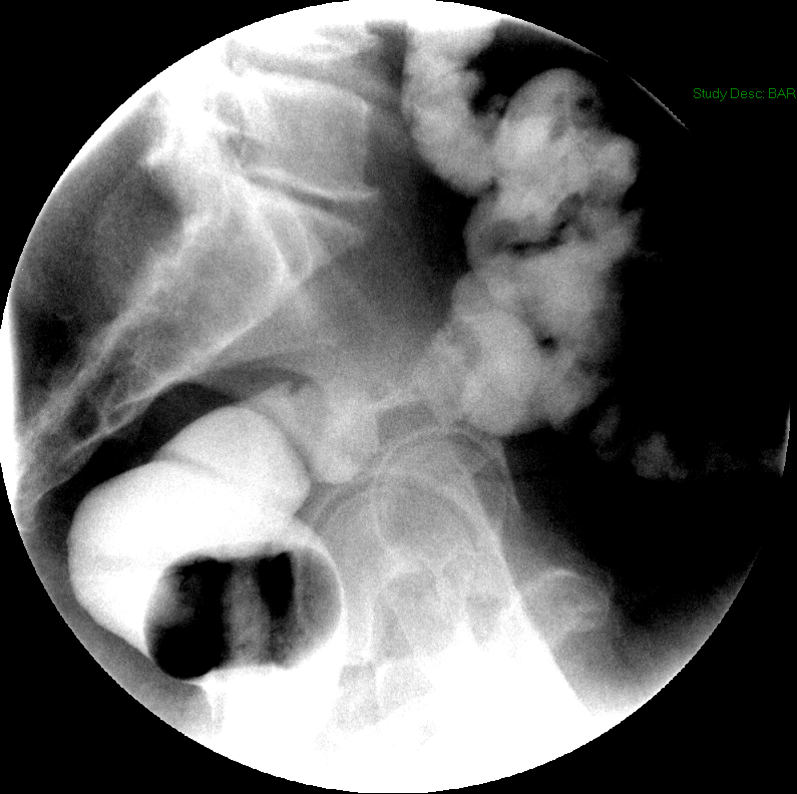

- The technologist will obtain a scout image. Assess the image for any possible contraindications such as pneumoperitoneum, evidence of ileus or obstruction, or residual contrast material

(key image 1).

- Once 15 minutes has passed since the patient drank the barium, the technologist will obtain a prone (if possible) radiograph

(key image 2).

- The technologist will obtain radiographs at 30, 45, and 60 minutes after the initial administration of barium. If the column of contrast material has not reached the large bowel on the 60 minute film, the technologist will obtain images every 30 minutes until contrast can been seen in the cecum

(key image 3)

(key image 4)

(key image 5).

- The technologist will have you review every image.

- Once the barium has reached the small bowel, you will go into the room and obtain spot images of the contrast material filled small bowel.

- Obtain images of the terminal ileum and the ileocecal valve filled with contrast material

(key image 6)

(key image 7)

(key image 8)

(key image 9)

(key image 10).

- Obtain spot images of the remainder of the small bowel

(key image 11)

(key image 12)

(key image 13)

(key image 14).

- Obtain images of all four quadrants. Use the compression paddle to separate loops of small bowel from each other.

- Evaluate for tethering of small bowel to any other structures.

- Observe for small bowel peristalsis.